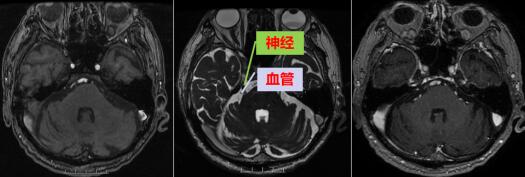

到医院后,医生给王大爷进行了仔细的检查,MR提示:右侧三叉神经版内段上方及内侧骑跨、穿行小血管与其关系密切;双侧面听神经颅内段示伴行及骑跨小血管影。